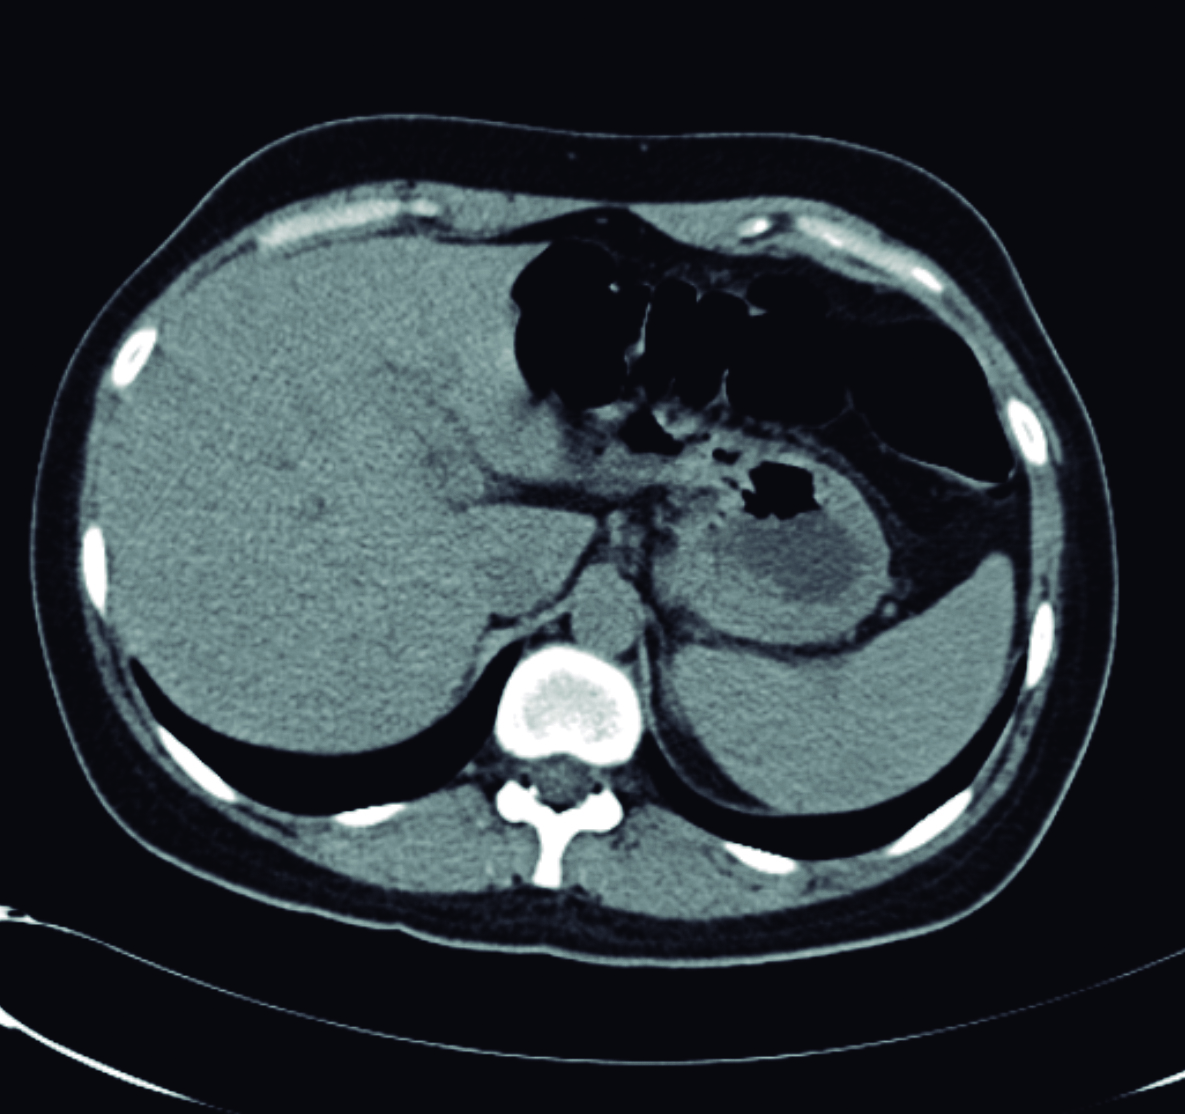

Con estos hallazgos, el equipo tratante solicita tomografía computarizada para completar valoración. La misma se realizó sin medio de contraste, dado dificultades en la punción de la paciente. Se observa imagen lineal hiperdensa dentro de la luz del colédoco, el cual se encuentra dilatado con un diámetro máximo 12mm (Fig. 2)

Figura 2. Tomografía computarizada plano axial sin medio de contraste

a y b) Se observa imagen lineal hiperdensa que corresponde al Ascaris dentro de la luz de la rama izquierda del conducto hepático y dentro del conducto hepático común (*).